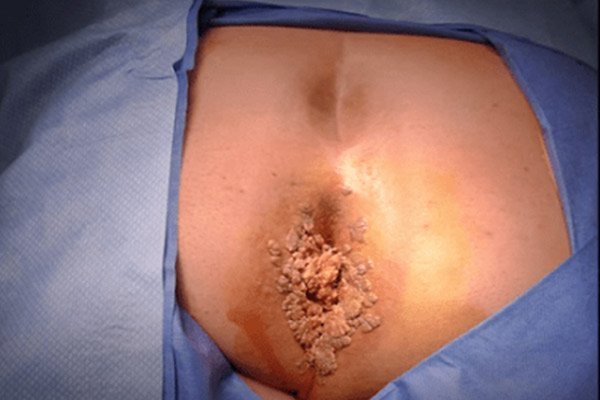

زگیل تناسلی برجستگیهای کوچک و گوشتی رنگی است که معمولاً در ناحیه تناسلی یا اطراف مقعد ظاهر میشود. این زگیلها به دلیل آلودگی به ویروس HPV ایجاد میشوند. بیش از 100 نوع ویروس HPV وجود دارد که برخی از آنها عامل ایجاد زگیلهای پوستی و برخی دیگر عامل زگیل تناسلی هستند.

برجستگیهای کوچک و گوشتی روی ناحیه تناسلی یا اطراف مقعد

عکس واضح از زگیل تناسلی زنان